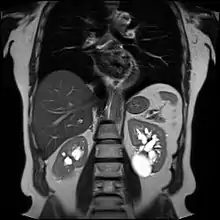

| Renal cyst | |

| Renal cyst of the left kidney (hyperintense area) as shown on MRI. | |